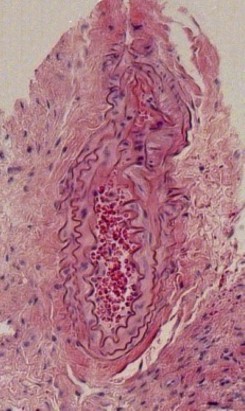

H&E (Haemotoxylin and Eosin) Staining

Ligation of Right External Carotid Artery Day-3 Post Procedure

Day-7 Post Procedure Day-14 Post Procedure Day-21 Post Procedure